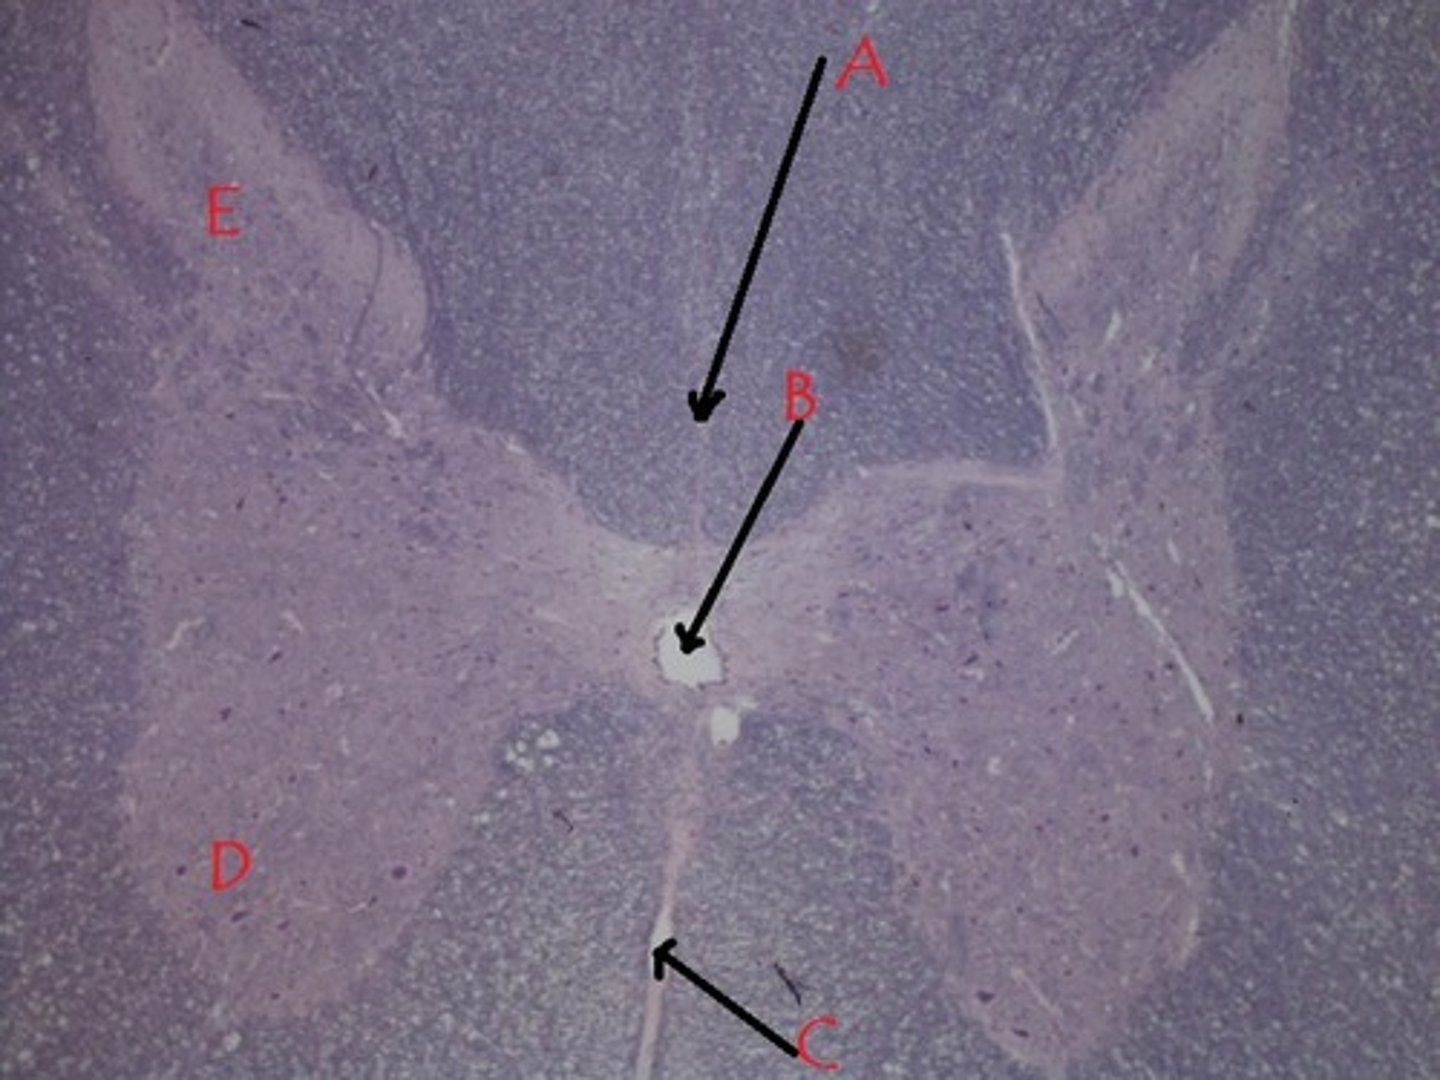

B

anterior median fissure

C

anterior gray horn

D

dorsal gray horn

E

posterior white column

V

lateral white column

W

anterior white column

X